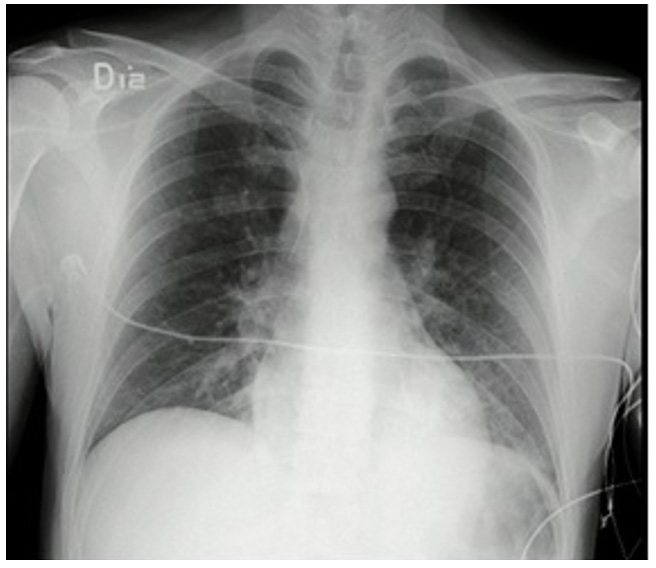

Frente a dichos resultados, se decidió trasladar al paciente a la unidad de cuidados intensivos para continuar el manejo médico con soporte ventilatorio. Por los hallazgos radiológicos de “vidrio esmerilado”, se le tomó la prueba de reacción en cadena de la polimerasa para SARS-CoV-2 en el contexto de pandemia, cuyo reporte fue negativo. Al ser valorado por el servicio de toxicología, este consideró que el cuadro, probablemente, se relacionaba con el consumo de cocaína. Luego de permanecer durante 48 horas con soporte ventilatorio, el paciente logró mejoría clínica, paraclínica y radiológica (figura 2), por lo que fue extubado sin complicaciones, con evolución favorable. Luego de ello se indicó su traslado a la unidad de hospitalización de psiquiatría, de donde egresó siete días después de su ingreso a urgencias.